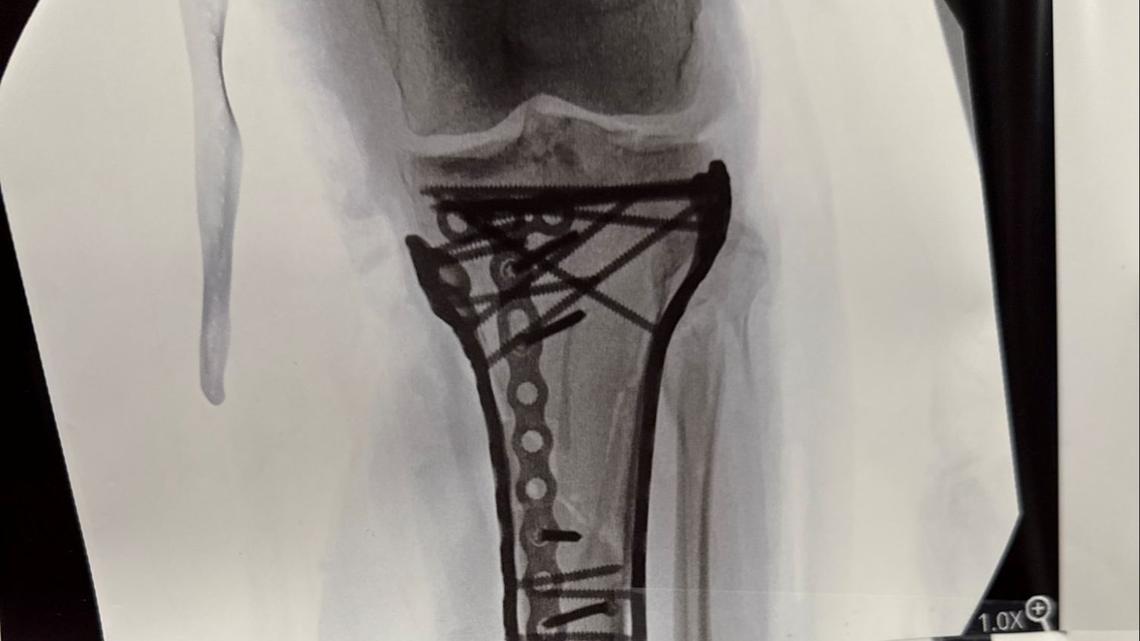

Lindsey Vonn and Her Doctor Recall Harrowing Process of Saving Her Leg

Lindsey Vonn Won't Discuss Her Skiing 'Future' After Devastating Leg Injury

Lindsey Vonn Shows Off Bandaged Leg During Workout After Olympics Crash